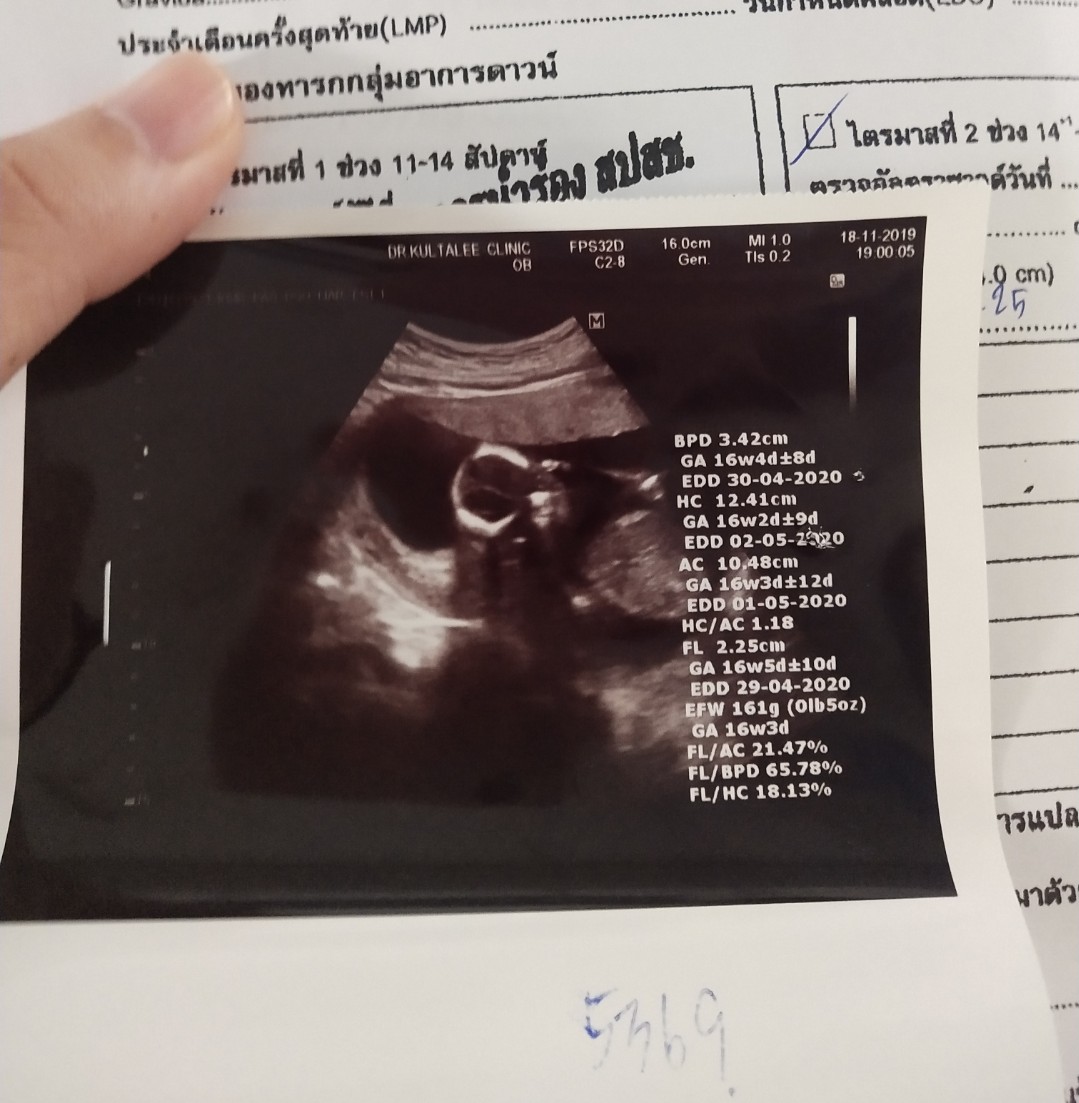

30 เม.ย.